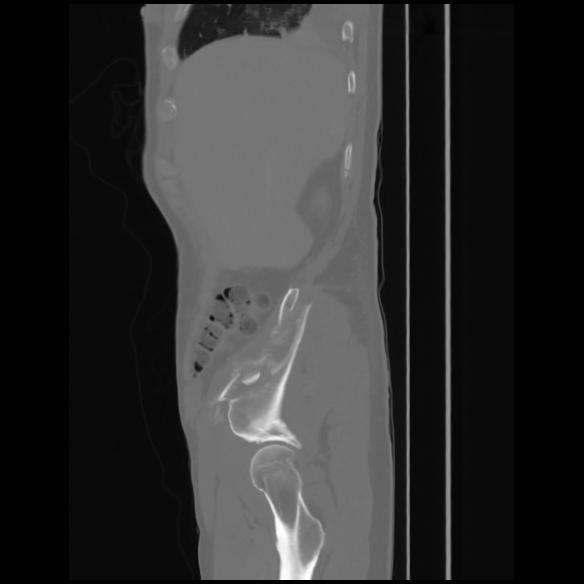

7 CUERPO,CE,Sagittal,3.000,CUERPO,Sagittal,